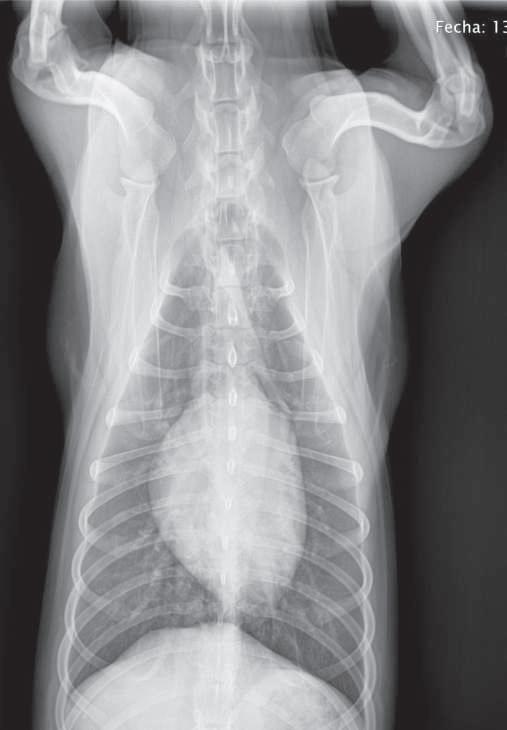

Estudio radiográfico con medio de contraste positivo (sulfato de bario), Li- Ld. Se observa que el medio de contraste pasó en su totalidad al estómago. (p.

Se presenta el caso de un perro doméstico, hembra esterilizada, raza única, de tres años de edad, con historia de presentar vómito crónico no responsivo a diversos tratamientos. La paciente no presenta anormalidad evidente en el examen físico general. Los estudios radiográficos, simples y con medio de contraste, no mostraron anormalidad aparente. Sin embargo, la endoscopía muestra, mediante la retroflexión del telescopio, la presencia de la mucosa esofágica dentro del estómago, lo que se consideró confirmativo de hernia hiatal, la cual se categoriza como tipo I. La gastropexia del antro pilórico resulta en un control completo del vómito. La hernia hiatal es la protrusión del esófago, la unión gastroesofágica o parte del fondo del estómago, hacia la parte caudal del mediastino, a través del hiato esofágico. Puede ser congénita o adquirida, permanente o dinámica; o, de acuerdo con su severidad, deslizante, paraesofágica, combinación de las dos anteriores y con herniación de órganos abdominales (correspondientes a tipos I, II, III y IV, respectivamente). Los signos dependen de la severidad pero comprenden regurgitación, vómitos o disnea. El diagnóstico se apoya principalmente en la fluoroscopía y la endoscopía. Los casos leves pueden tratarse únicamente con antiácidos y procinéticos. No obstante, la cirugía (frenoplastía, esofagopexia y gastropexia) a menudo es necesaria para un efectivo control de los signos.

tivo, en un intento de diferenciar vómito de regurgitación, se realiza estudio radiográficosimple(sincambiosradiográficos aparentes) (Figuras 1 y 2) yconmediode contraste (sulfato de bario) (Figura 3); se encuentra un tránsito normal del esófago y del estómago.